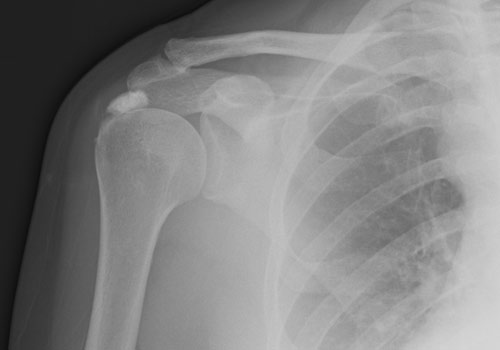

A plain x-ray of the shoulder joint can show calcification of the tendons around the shoulder.

MRI scan when used to look for other problems in the shoulder, e.g. tendon tears, can also show the calcium deposits inside the tendons.